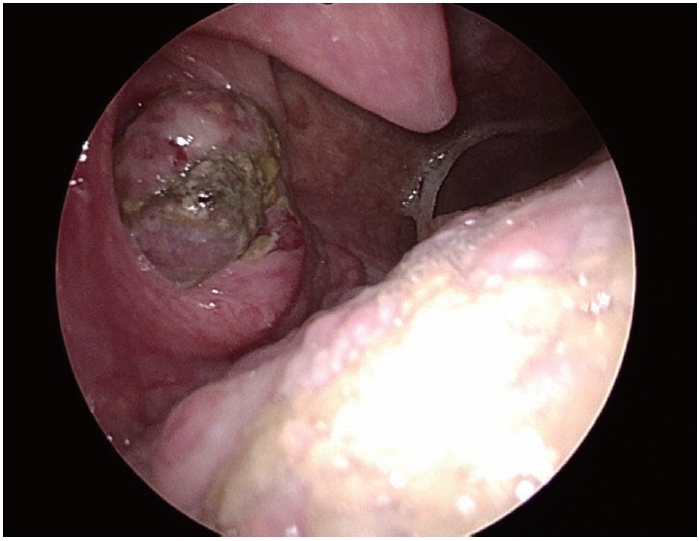

Contrast-enhanced neck CT showed a peripherally enhancing lesion with central low attenuation (1.8 cm) in the right palatine tonsil (Fig. 2A), and neck MRI showed a lobulated mass (2.3 cm) at the same site with low T1 signal intensity and intermediate T2 signal intensity (Fig. 2B). There was no local invasion and there were no notable findings in the cervical lymph nodes.

For staging and treatment planning under suspicion of a primary tonsillar malignancy, chest CT revealed a 3.8 cm lobulated mass extending across the left major fissure and pleura (Fig. 2C) and a 4.3 cm enlarged lymph node in the left hilum. PET-CT demonstrated fluorodeoxyglucose-avid lesions in the right tonsil (SUVmax 21.64), left lower lobe lung (SUVmax 26.41), left hilum (SUVmax 29.64), and small intestine (SUVmax 16.55) (Fig. 2D).

NotesAcknowledgments This case report was approved by the Institutional Review Board (IRB No.: EUMC 2025-09-061). Author Contribution Conceptualization: Han Su Kim. Data curation: Eun Bin Lee. Investigation: Eun Bin Lee. Methodology: Han Su Kim. Project administration: Eun Bin Lee. Resources: Han Su Kim. Supervision: Han Su Kim. Validation: Han Su Kim. Writing—original draft: Eun Bin Lee. Writing—review & editing: Han Su Kim. Fig. 1.Endoscopic view at the initial outpatient evaluation showing an ulcerative, protruding mass in the right palatine tonsil. Fig. 2.Radiologic findings. A: Contrast-enhanced neck CT showing a 1.8-cm peripherally enhancing, centrally low-density lesion in the right palatine tonsil (yellow arrow). B: Neck MRI showing a 2.3-cm lobulated mass in the right palatine (yellow arrow) tonsil with intermediate T2 signal intensity. C: Chest CT showing a 3.8-cm lobulated mass (yellow arrow) extending across the left major fissure and involving the adjacent pleura. D: PET-CT demonstrating fluorodeoxyglucose uptake in the right palatine tonsil (yellow arrow, SUVmax 21.64), left lower lobe lung lesion (blue arrow, SUVmax 26.41), left hilar lymph node (blue arrow, SUVmax 29.64), and small intestine (green arrow, SUVmax 16.55). Fig. 3.Pathologic findings from the right palatine tonsil biopsy. A: Hematoxylin-eosin–stained specimen showing poorly differentiated carcinoma, favoring metastatic non-small cell lung carcinoma (original magnification ×100). B: Immunohistochemical specimen showing diffuse positivity for cytokeratin pan (CK-PAN), supporting epithelial origin (original magnification ×100). C: Immunohistochemical staining for P40 showing negative results, arguing against a primary squamous cell carcinoma of the tonsil (original magnification ×100). D: Immunohistochemical specimen showing focal vimentin expression, which can be observed in poorly differentiated carcinomas with partial mesenchymal features (original magnification ×100). Fig. 4.Post-treatment radiologic assessment following CCRT. A: Follow-up neck CT showing no residual enhancing mass in the right palatine tonsil (yellow arrow). B: Follow-up chest CT showing a decreased size of the previously noted lobulated mass (yellow arrow) extending across the left major f issure. REFERENCES1. Unsal M, Kutlar G, Sullu Y, Yurtlu S. Tonsillar metastasis of small cell lung carcinoma. Clin Respir J 2016;10(6):681-3.